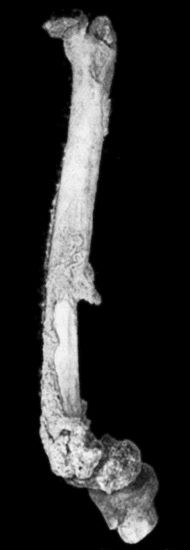

432 118.Shaft of the Femur after Acute Osteomyelitis

444 119.Femur and Tibia showing results of Acute Osteomyelitis